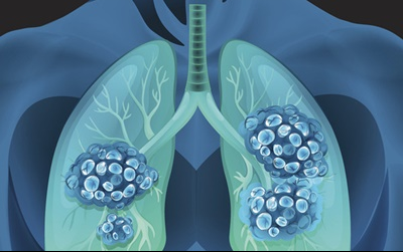

이번 기사에서는 폐암 초기 증상에 대해 자세히 정리해 알려 드리겠습니다 . 폐암은 국내암 사망률 1 위로, 과거에는 흡연이 폐암의 주된 원인 이었지만 , 현재는 비흡연 폐암 환자도 대폭 증가했습니다 . 폐암은 의학 기술로 발달하여 생존율이 높아지고 있습니다 . 폐암의 초기 증상은 무엇인가를 알아보겠습니다.

폐암의 초기 증상